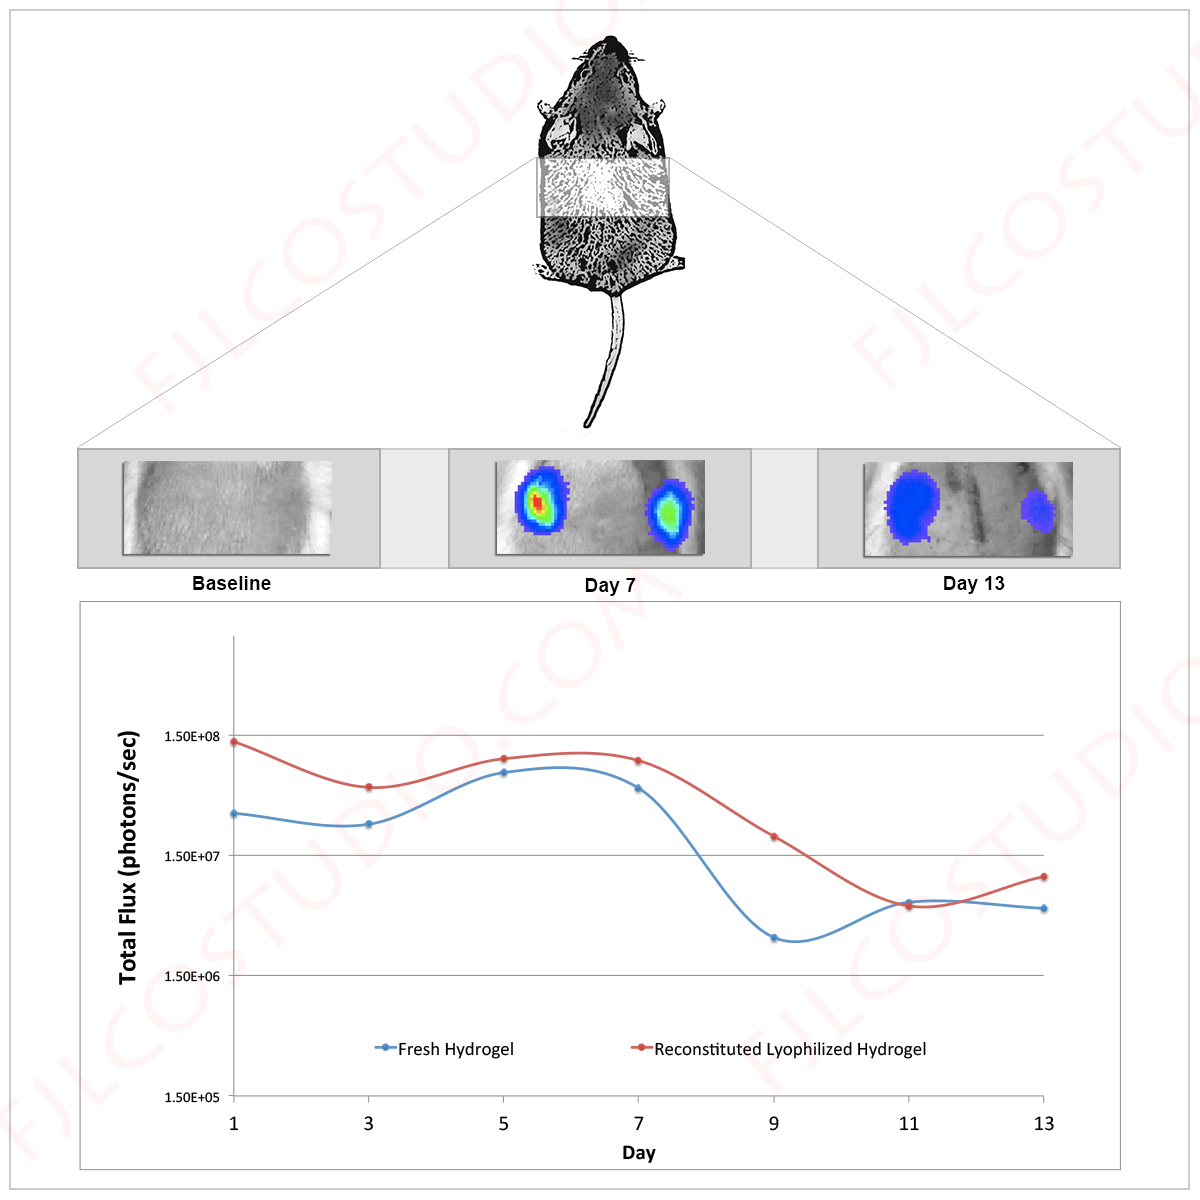

Hi designers, I'm working on a paper for publication in a peer-reviewed medical journal. As part of this project, we must include a number of figures that illustrate the data we collected. I am looking for a designer to help put together one of these figures aesthetically. This figure is supposed to provide context about how we performed the experiment and also show the graph. There are 3 components to this figure: 1.) A schematic drawing of a rat with the area of the back with a box around it which projects to three boxes below. 2.) These boxes are three side by side images at different time points. 3.) Below this is a graph which illustrates the boxes quantitatively. Attached is a file "layout.jpg" which is a crude drawing of what all of this should look like. The files #1-3 are the boxes (as described in number 2). And the #4 is the graph (as described in number 3) as a pdf. Please create the graphic in as high a resolution as possible. Attached is "Sample_Figure.jpg" which shows the style in which the rat should be drawn.